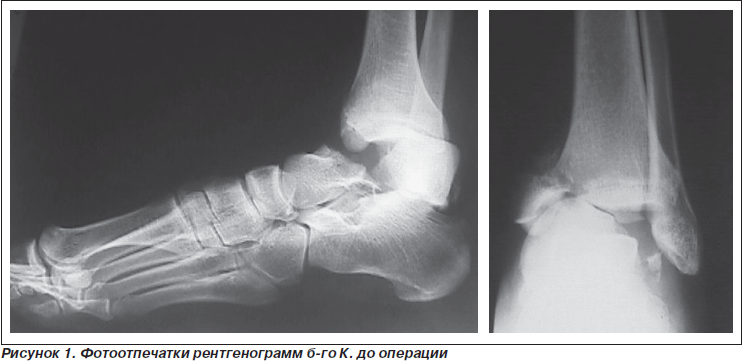

Больной К., 34 года, поступил в клинику НИИТО в ургентном порядке по поводу закрытого оскольчатого центрального переломовывиха таранной кости (тип IV), оскольчатого перелома внутренней лодыжки слева со смещением. Травма в результате ДТП. Больной, водитель легкового автомобиля, доставлен СМП с транспортной иммобилизацией. В ургентном порядке выполнена операция: открытая репозиция переломовывиха таранной кости из внутреннего доступа через линию перелома внутренней лодыжки с остеосинтезом спицами и винтом, в комбинации с чрескостным остеосинтезом. Послеоперационный период без особенностей, рана зажила первично. Диафиксационные спицы удалены через 5 недель, установлены шарниры, разрешена осевая нагрузка и разработка движений. Фиксация в АВФ в течение 3,5 месяца. Консолидация достигнута, анатомо-функциональный результат удовлетворительный.